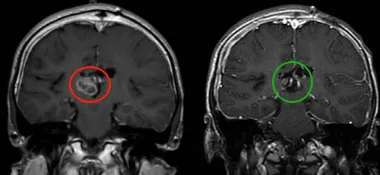

第一次左額半球間經(jīng)胼胝體切除術(shù)后,CT掃描顯示腦室內(nèi)和腔內(nèi)出血。第二次經(jīng)右頂葉經(jīng)皮質(zhì)入路成功實現(xiàn)次全切,術(shù)后顯示為WHO 2級室管膜瘤。隨后,為進(jìn)一步控制殘余腫瘤,魯特卡教授為患兒制定了局部放療方案。

幾年后,隨訪時發(fā)現(xiàn)腫瘤再次生長,因此在部分切除后再次進(jìn)行放療。此后6年,室管膜瘤無復(fù)發(fā),病情穩(wěn)定。